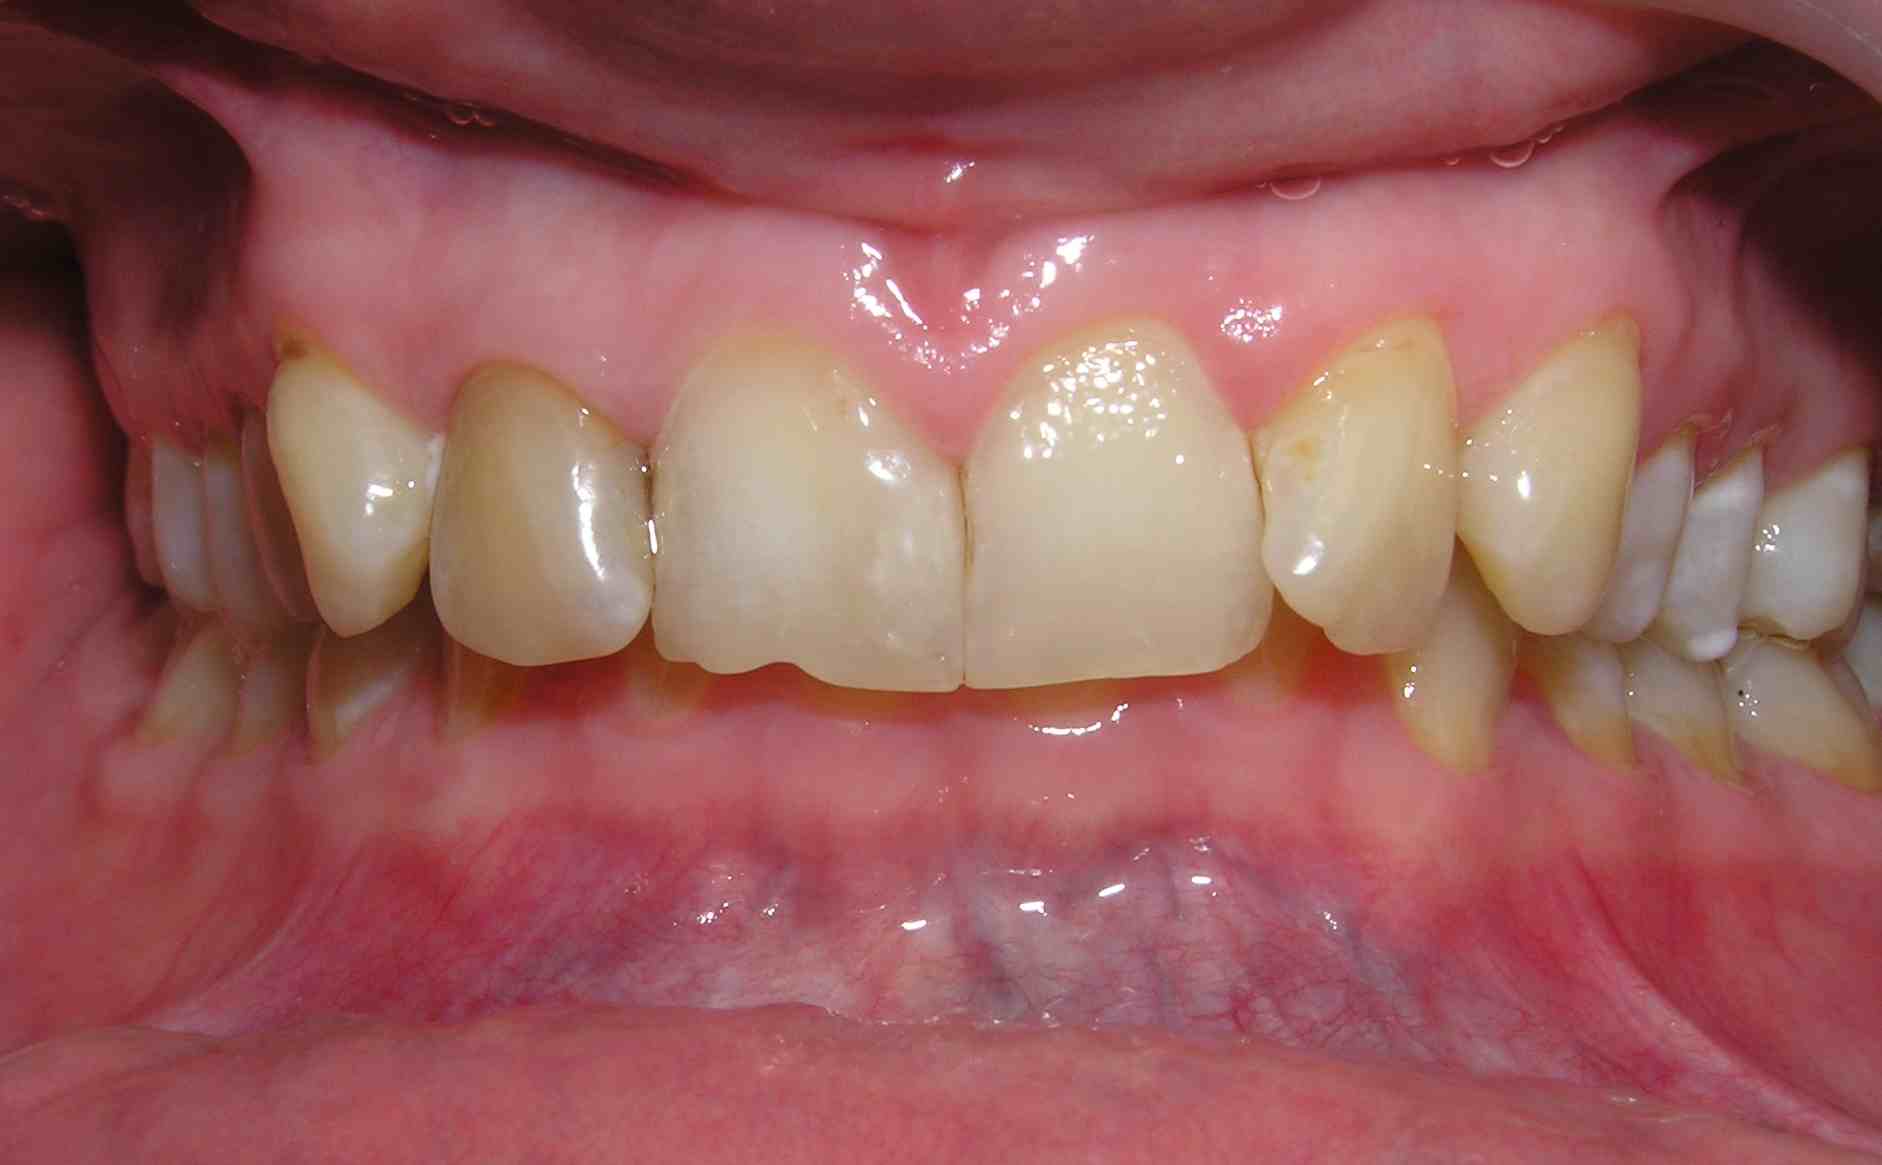

Pic.16. Mesial position of tooth 11 with lack of space in the dental arch.